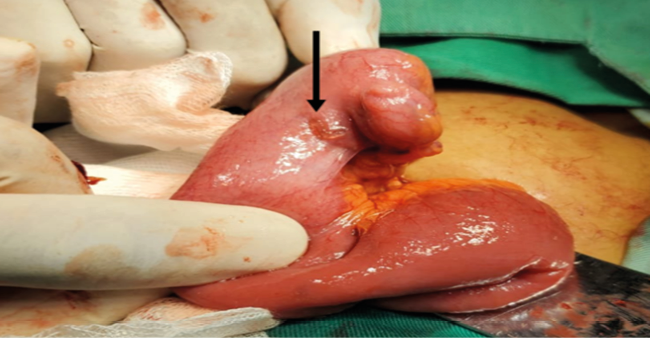

The patient was prepared for emergency surgery in the operating room, with a presurgical diagnosis of uncomplicated acute appendicitis. The surgical intervention, classified as class II surgery, was performed on 02/20/23 by Surgeon Dr. Mejía (Basic Physician), with the first assistant Dr. Hernández (Third Year Resident), and the second assistant Dr. González (Second Year Resident). Regional anesthesia (0.5% heavy bupivacaine, 15 ml administered in the epidural space at the level of the lumbar region) and preoperative sedation (Midazolam, initial dose: 3ml intravenously and maintenance dose 3ml every hour) were administered by anesthesiologist Dr. Martínez, who performed the spinal block. The intervention lasted one hour and ten minutes [Start 2:30 p.m. - End 3:40 pm]. The patient, in the supine position, underwent an appendectomy by conventional means of a McBurney incision. The transoperative findings (Table 1) confirmed the preoperative diagnosis of acute appendicitis, corroborating that the disease was in the suppurating phase, which was the cause of the acute abdomen. Incidentally, a solitary Meckel’s diverticulum, located 80 cm from the ileocecal valve, measuring 2x2 cm, was found. No perforation, ulceration of the ileal mucosa, inflammatory reaction, or fibrous bands obstructing the intestinal lumen were observed (Figure 1). A diverticulectomy was performed using the wedge resection technique with primary anastomosis. Both specimens (vermiform appendix and Meckel’s diverticulum) were sent to the pathology department for histopathological analysis. The patient’s transoperative evolution occurred without any eventuality, ending the intervention successfully.

Figure 1

Meckel’s diverticulum observed in case1

Note: The arrow in the figure shows Meckel’s diverticulum observed in the patient in case 1.

Source: Archive of images captured during operating room procedure